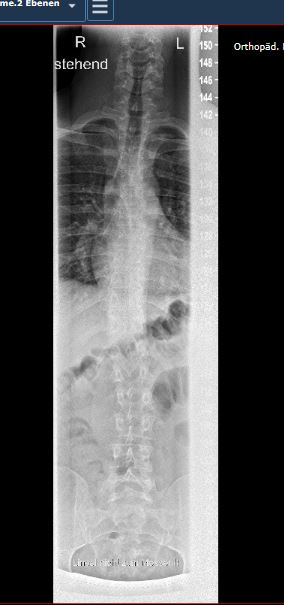

Im Befund steht: BWS Keine skoliotische Fehlhaltung. Keine vermehrte Kyphosierung. Normalweite Bandscheibenwirbelräume. Kein Hinweis auf Keil oder Blockwirbelbildungen. Kein Anhalt für stattgehabten M.Scheuermann. Kein Hinweis auf osteoporotisch bedingte Frakturen. Minimale Skoliose von 6 Grad.

LWS 04/16 Angedeutete rechtskonvexe Lumbalskoliose mit einem Cobb winkel von 3 Grad. Normalgliedrige LWS. Unvollständiger Bogenschluss von L5. Normalweite Bandscheibenzwischenräume. Keine Spondyliosthesis.

Am Freitag war ich im König-Ludwig-Haus in WÜ wegen eines Fußproblems. Aber sie wollten eine komplette WS-Ganzaufnahme im Stand. 2 Ebenen.. Das Bild wo ihr seht ist akutell von Freitag. dem 04.11. Leider sagte die Ärztin nur dass man dies auf einem MRT nicht so deutlich sehen würde. Und nur dass man es konservativ behandelt. Der niedergelassene hat immer im STEHEN geröntgt. Nehme schmerzmittel mache übungen rehasport an geräten ZNS Bobath und normale KG übungen zU hAUSE

- WS_DM.JPG (29.44 KiB) 5896 mal betrachtet